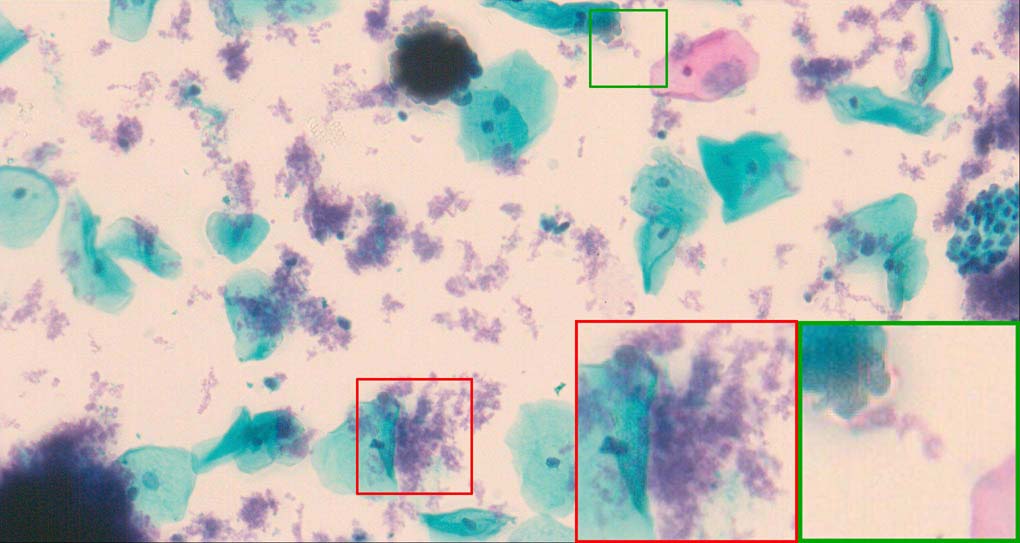

A good image fusion method should contain the following properties. First, it preserves both the details of small size objects and the integrity information of large size objects in the fused image, even in the case of the size of the interested objects varying largely in the image. For example, the cervical cell images from the microscope contain both small size isolated cells and large size agglomerates, which are both useful for cervical cytology [5]. Second, it should be efficient enough to handle large-scale data. For instance, it needs to process thousands of fields of view (FoV) in an acceptable time for the whole slide scanning in digital cytopathology [6], which requires to fuse a series of high resolution images captured at each FoV in a very efficient way. Third, it does not produce obvious artifacts. Despite being studied extensively, to our best knowledge, existing fusion methods may not meet these requirements simultaneously.

To demonstrate the effectiveness and efficiency of the proposed image fusion method , we conduct a set of comparative experiments on three image datasets. The first is composed by 8 pairs of multi-modal medical images and the second one contains 15 pairs of multi-focus gray or color natural images. These two datasets are often used in many related papers and some examples are shown in Figure 3(a) and Figure 3(b). The third one is a new multi-focus cervical cell image dataset collected by ourselves, which consists of 15 groups of color images and each group contains a series of multi-focus cervix cell images with size of or , etc. Some source examples are shown in Figure 3(c). Our source code implemented in C++ along with the new multi-focus cervical cell image dataset is available online.

Figure 9, Figure 10 and Figure 11 show the comparative fused results of the multi-focus cell images shown in Figure 3(c). For clarity, we also present a closeup view in the right-bottom of each sub-picture in Figure 9 and Figure 10. As shown in the close-up views of Figure 9, the fused images based on DSIFT, IM, MWGF and BF methods are extremely blurred in the boundary and fail to keep the details of cell nucleus. Furthermore, the DTCWT and NSCT based methods produce halo artifacts in the fused images, while GFF and CNN based methods fail to preserve the small cell nucleus. LP-SR based method nearly works fine which keeps the most of the details of the small size cells, but the integrity of the clustered large size cells is damaged. Fortunately, in our proposed method, the integrity of the clustered large size cells is preserved and most of the isolated small size cells are maintained from the original images, which demonstrates the best visual quality.

Similarly, as shown in the close-up views of Figure 10, the fused images from DSIFT, IM, MWGF and BF are blurred and lose some nucleus details, while the results from DTCWT, GFF, CNN and NSCT produce halo artifacts. LP-SR based method can keep details well but also produces halo artifacts and other noise. Our method can preserve the focused areas of different source images well without introducing any artifacts. For the example illustrated in Figure 11, the fused images generated by DSIFT, DTCWT, IM and NSCT all fail to preserve the focused areas of different source images and result in extremely blurred images. The GFF, CNN, MWGF and BF based method introduces a lot of color distortion of the nucleus regions and the obvious halo artifact. The result of LP-SR based method is close to the one of our method but introduces some odd color distortion. Again, our method produces fused image which can preserve the focused areas of different source images well without introducing any artifacts.